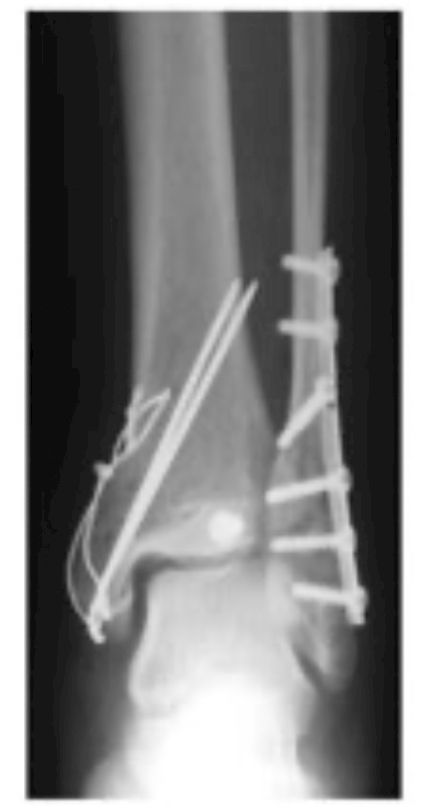

もともと

若い頃に

右足首の[くるぶし]を

粉砕骨折して

⬆︎

こんな処置をしてもらっていたので

足首自体

あんまり強くない

ヒールがない靴で歩けないのは

そのせい